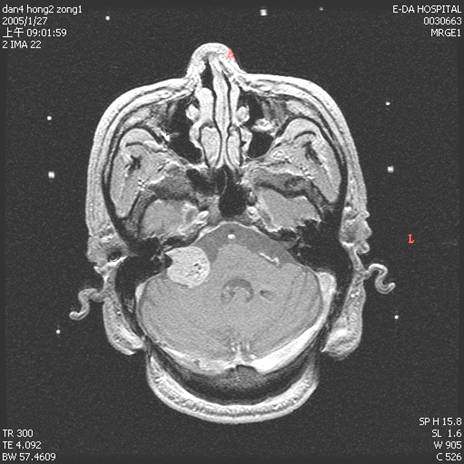

轉移性腦瘤

手術前

手術後